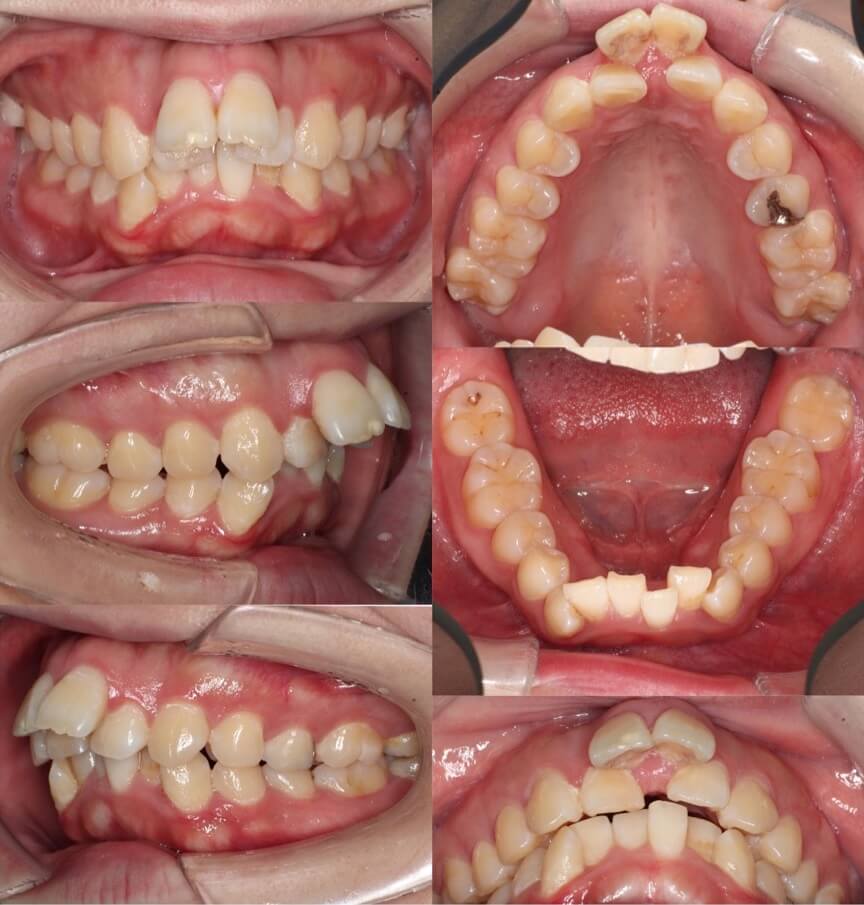

高校生女性・唇側矯正装置・上抜歯

上の前歯が前に出ているため下唇に当たり口が閉じづらいという症状を、抜歯を併用して前歯を引っ込めて治しました。術後は奥歯を含めて理想的なかみ合わせになり、スマイルも大きく変化しました。ご本人からも大変満足していただけました。少し前歯が小さめですが、唇側矯正装置であればしっかりと歯の動きをコントロールする事ができます。

<症例概要> 難易度★★★☆☆

主訴:出っ歯

年齢・性別:高校生女性

住まい:千葉県船橋市

症状:上顎前突・叢生・過蓋咬合・右側シザースバイト

治療方針:上抜歯空隙閉鎖(中等度固定)・ストリッピング

治療装置:唇側矯正装置

固定装置:ナンスホールディングアーチ

抜歯:上第一小臼歯(計2本)

治療期間:2年2か月

リテーナー:上プレートタイプ+クリアタイプ・下フィックスタイプ

治療費用:968,000(税込)

代表的副作用:痛み・治療後の後戻り・歯根吸収・歯髄壊死・歯肉退縮